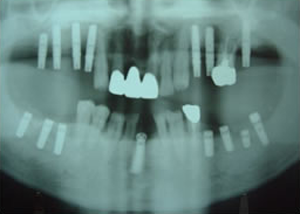

5.終了時レントゲン

治療完了

平成19年5月1日

(治療期間:2年10ヶ月)

1.・骨つくり

・インプラント15本埋入

ソケットリフト

サイナスリフト

リッジオギュメンテーション